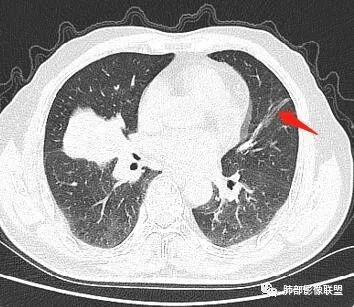

主病灶在中叶,但是左肺舌段叶有条索影,陈旧病变。蓝色箭头支气管受压,是淋巴结肿大

主病灶在中叶,但是还有结节状病变在下叶

左下叶背段小结节,舌段索条,内似有扩张支气管